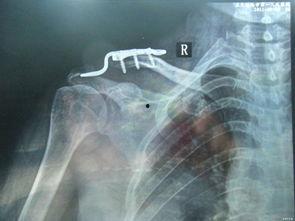

1. 手术过程视频:这类视频详细展示了手术的整个过程,包括麻醉、手术器械、手术步骤等。通过这些视频,你可以直观地了解手术的全貌。

2. 术前术后对比视频:这类视频展示了患者手术前后的变化,让你对手术效果有一个直观的认识。